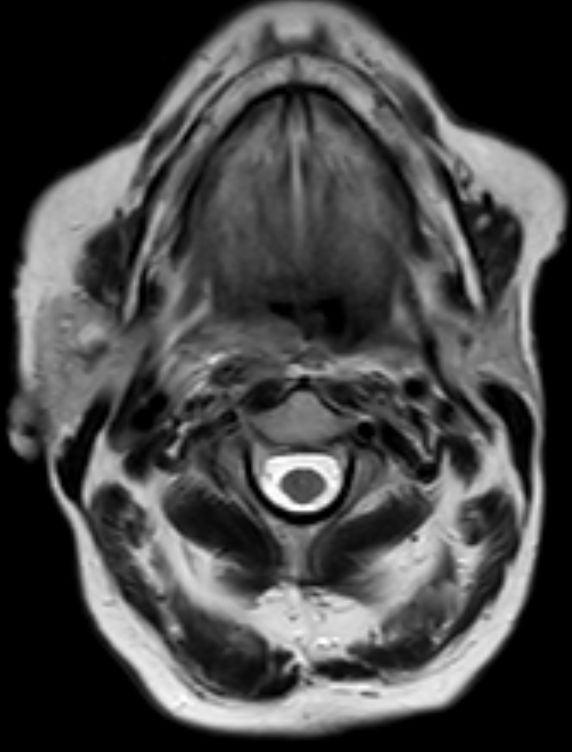

| Diagnostik | 88-jährige Frau mit einer progredientes

Dysphagie. Es besteht eine Raumforderung rechts retropharyngeal. Mukosa intakt.![]() |